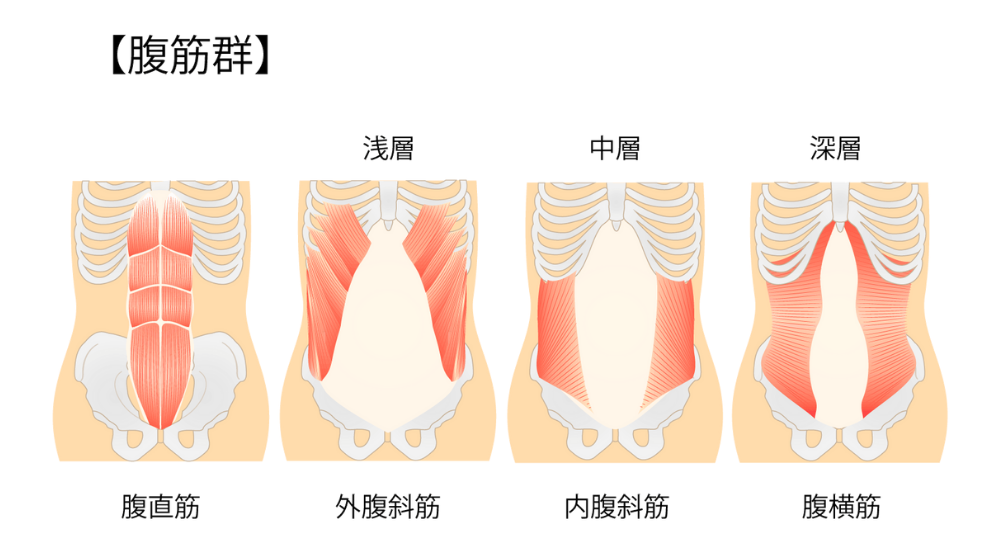

例えば、猫背の姿勢では、背中の筋肉(特に脊柱起立筋や菱形筋)が常に引き伸ばされた状態になり、逆に身体の前面(大腰筋や腹筋群)は縮こまりやすくなります。

このような筋肉のアンバランスが生じると、関連する筋膜も引っ張られたり縮んだりして、柔軟性を失い硬くなっていきます。

なぜ、あなたの腰ばかりが疲れてしまうのでしょうか? それは、本来働くべきお腹のインナーマッスル(腹横筋)や、お尻の筋肉(大殿筋)が“サボって”いるため、その仕事をすべて腰の筋肉が肩代わりしている「代償動作」が起きているからです。 私たちは、詳細な動作検査や筋力検査で、この「サボり筋」を正確に特定します。腰だけを施術するのではなく、お腹やお尻の筋肉が再び正しく使えるように働きかけることで、腰への過剰な負担を根本から解消します。